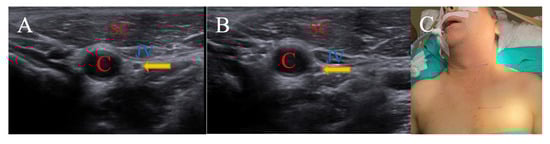

3.1.1. Contralateral Head Rotation for Nervus Vagus

3.1.2. Neutral Position for Sternocleidomastoid Muscle

3.1.3. Neutral Position for Nervus Vagus

| SCM | Sternocleidomastoid |

| C | Carotid artery |

| JV | Jugular vein |